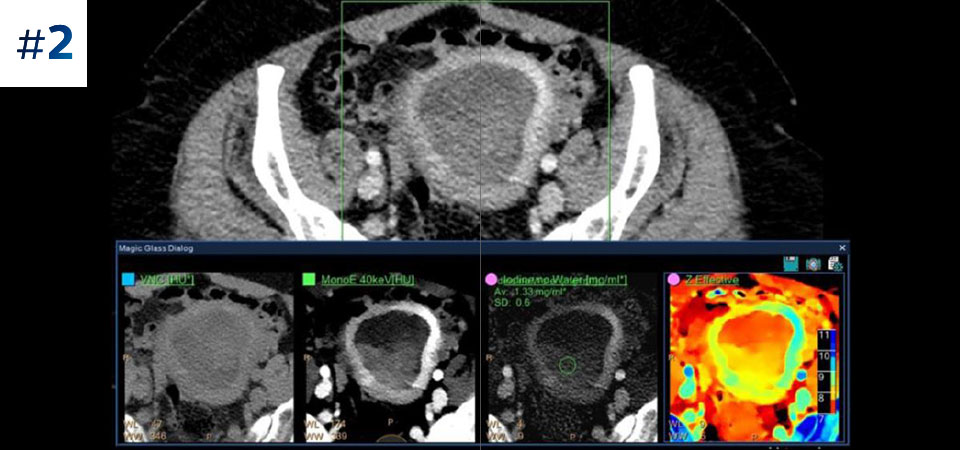

Nuestro CT con detección espectral de Philips, nos permite adquirir datos convencionales y espectrales en una sola exploración, sin cambios en nuestro flujo de trabajo actual.

Observe las diferencias entre un detector espectral CT y un CT Convencional

Aprenda sobre las ventajas del detector espectral CT